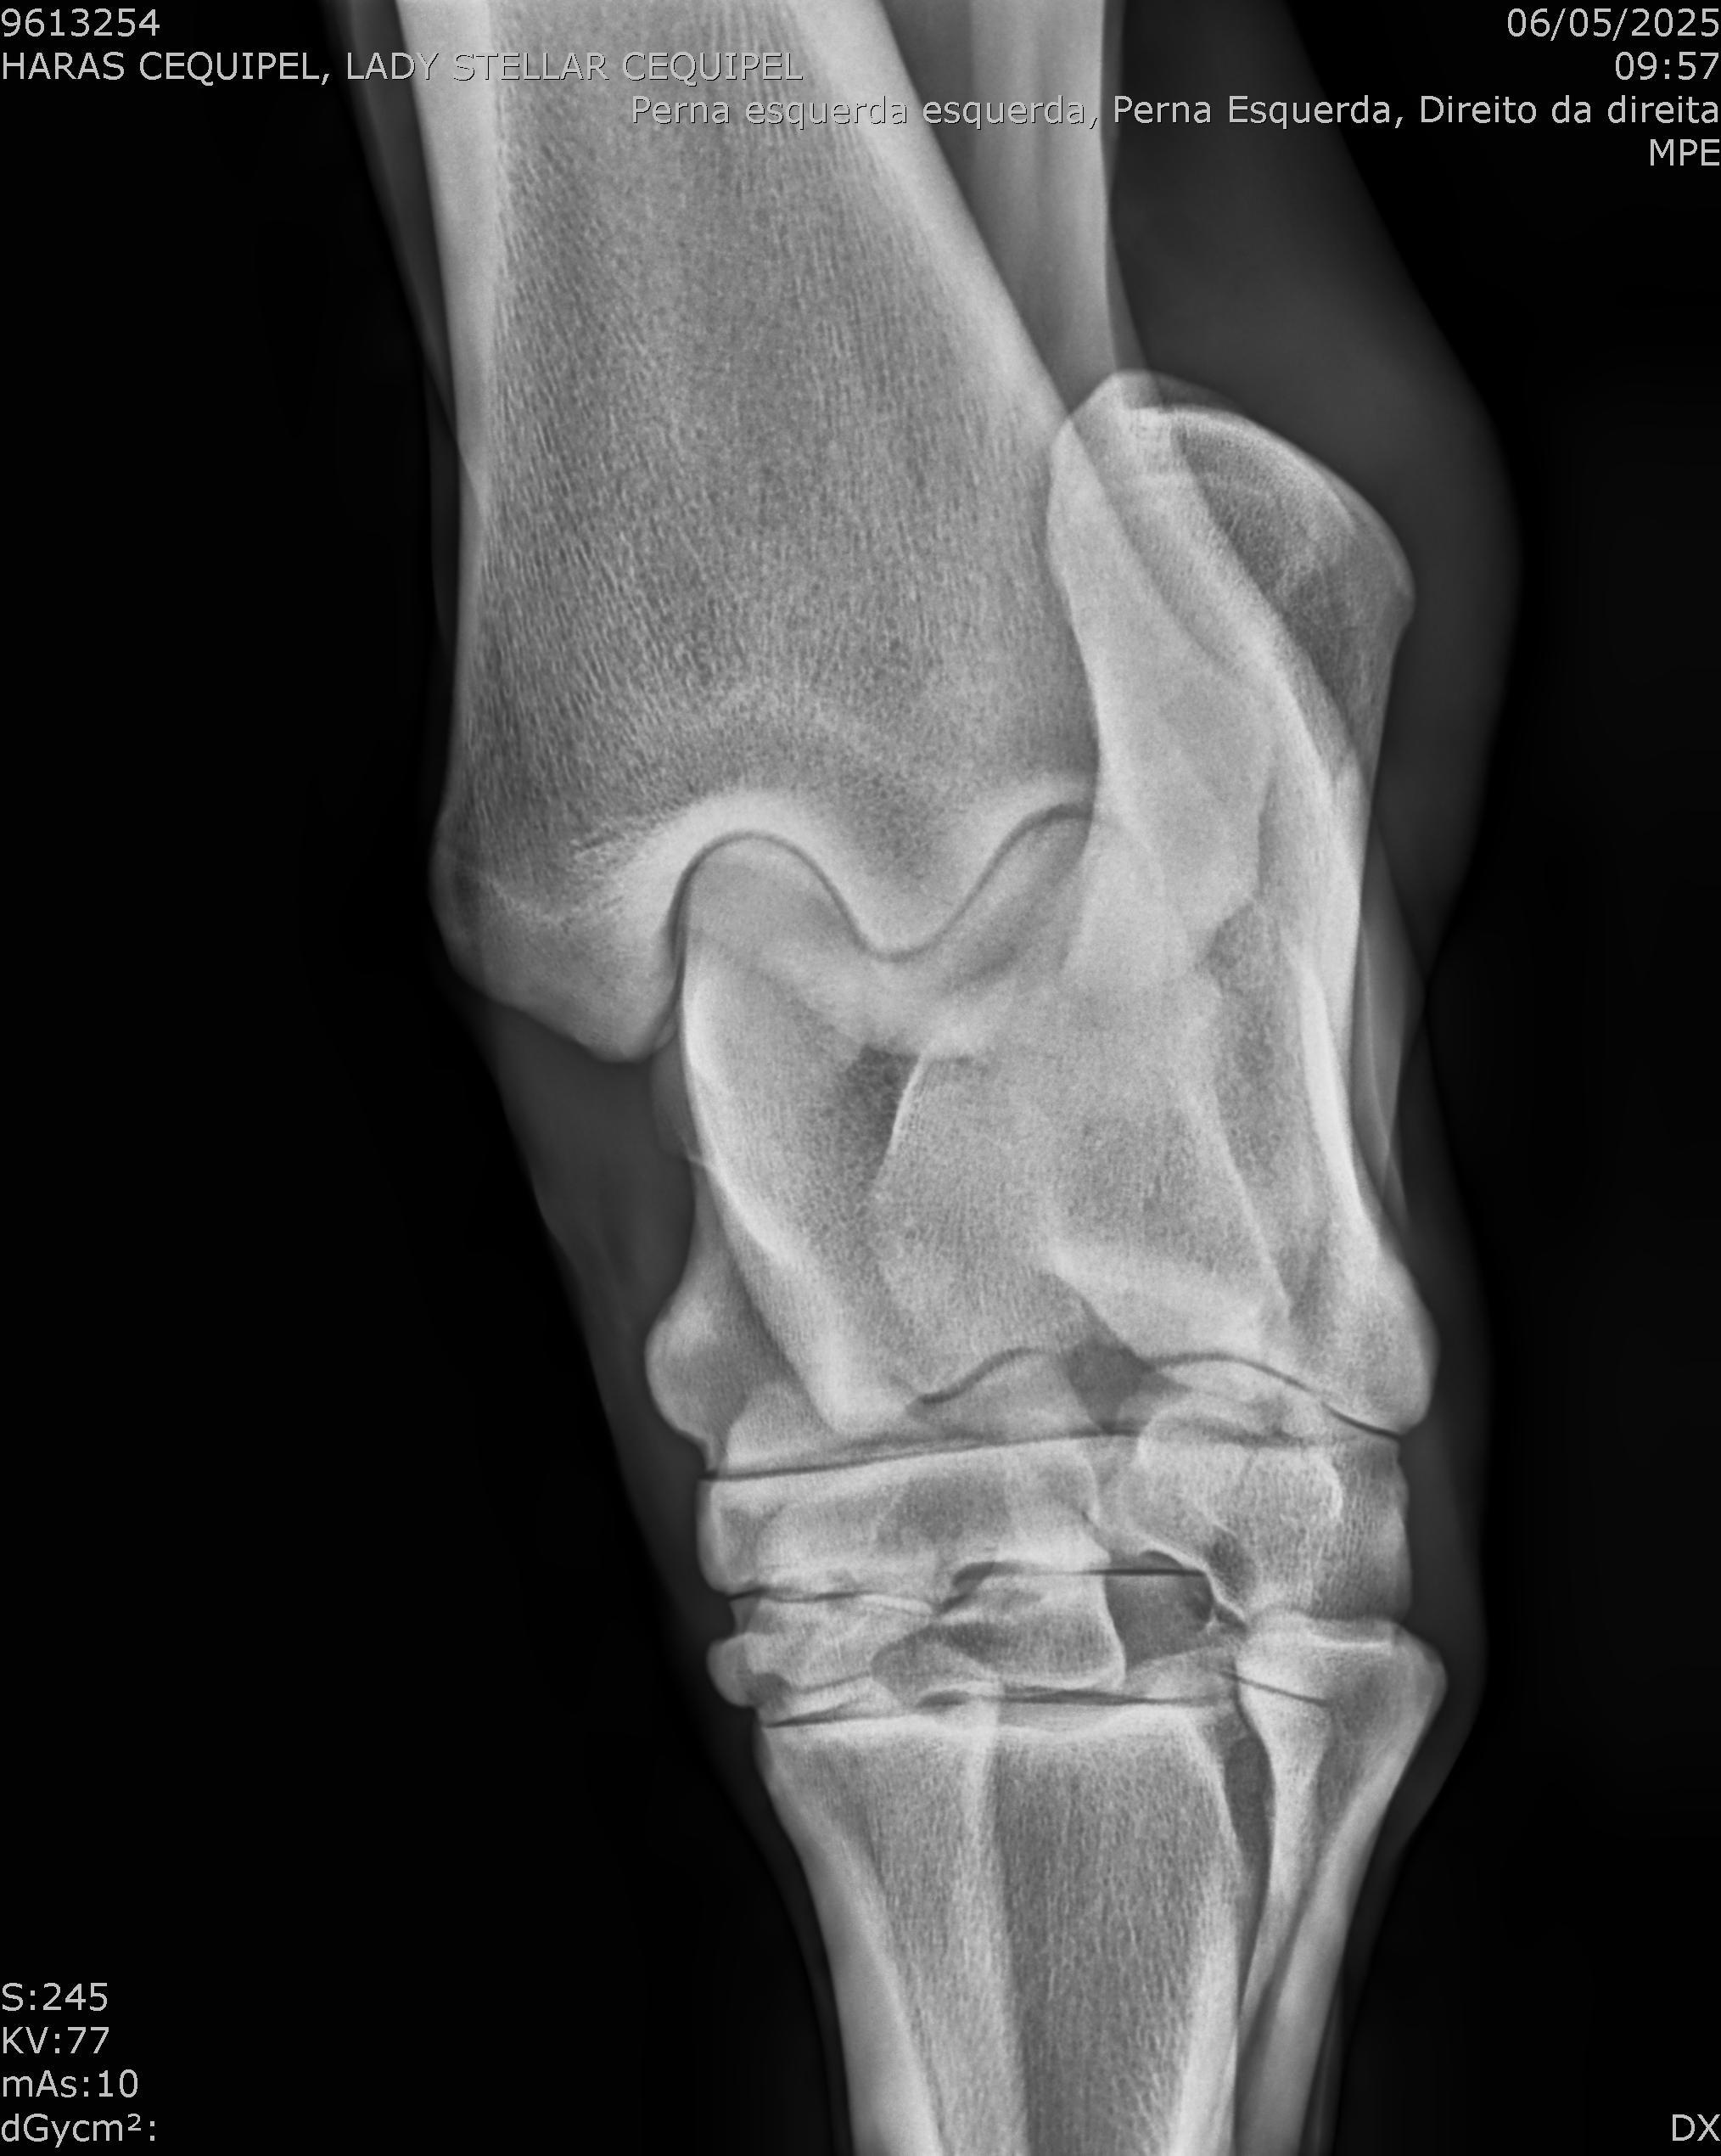

:: RAIOS-X DO LOTE